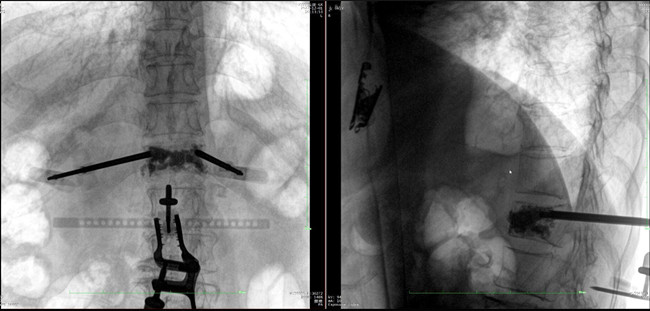

骨科機器人影像

*骨水泥置入效果良好